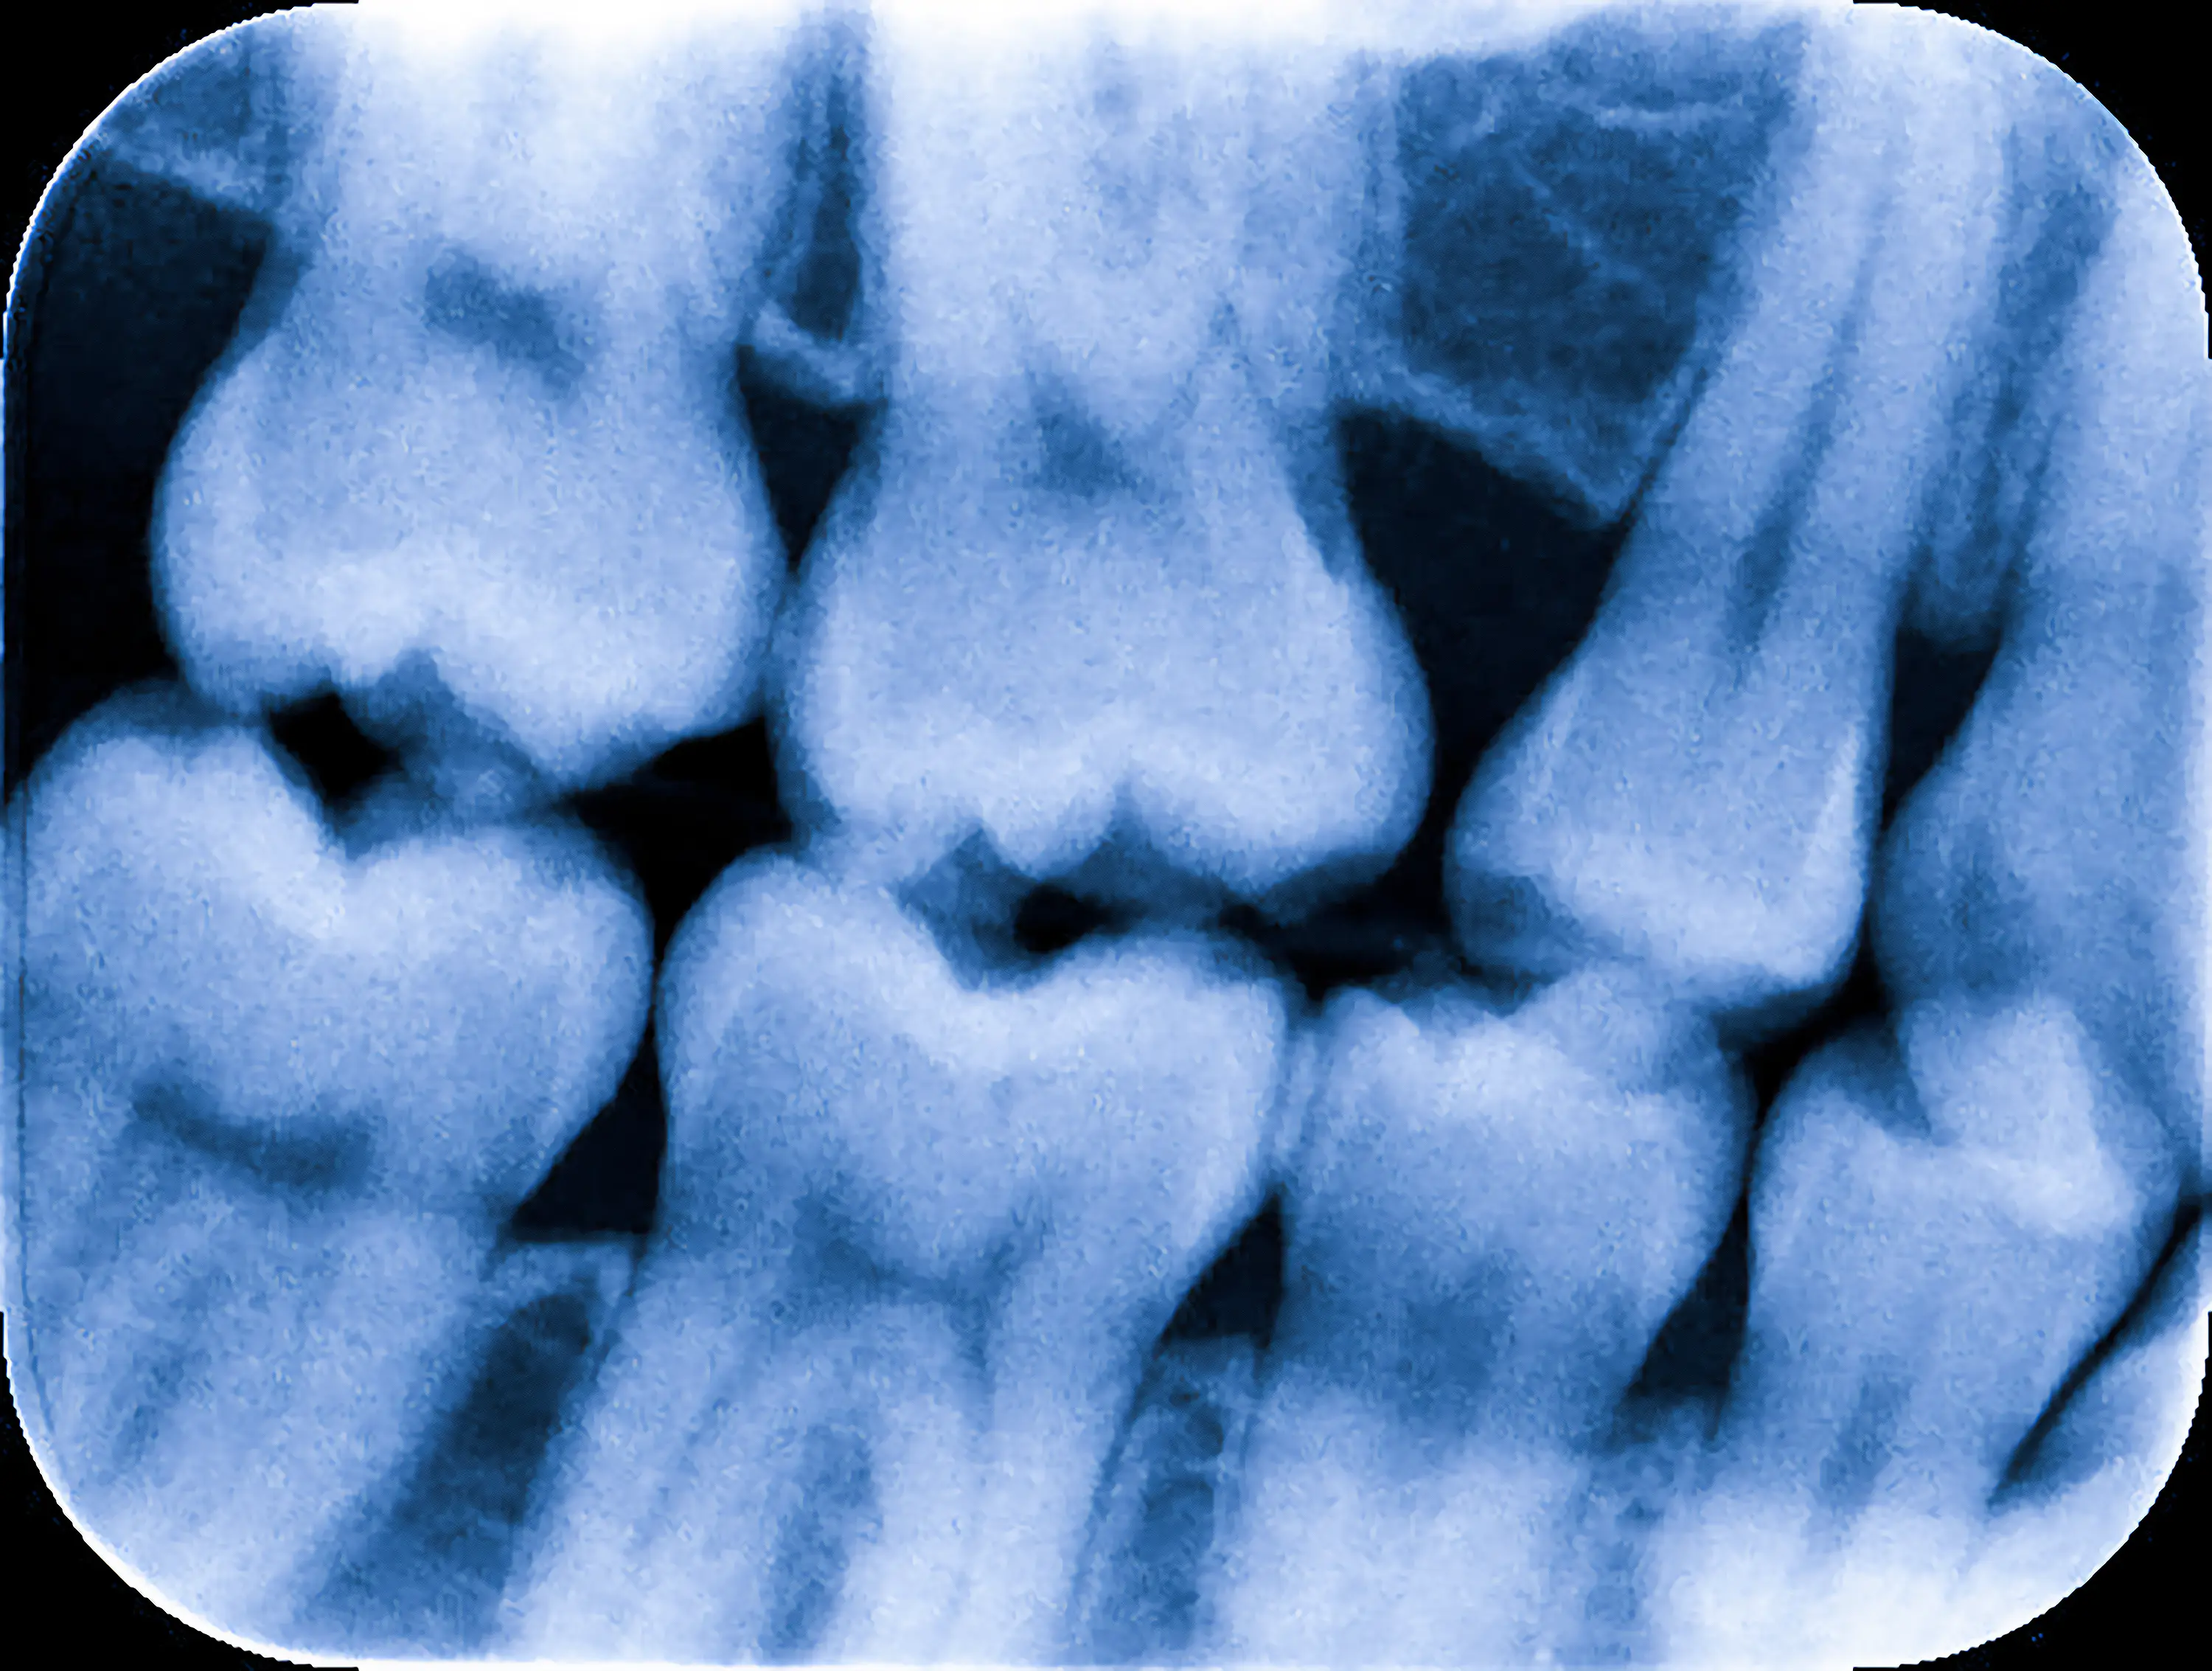

Rentgenodiagnostyka to kluczowy element nowoczesnej stomatologii, pozwalający na precyzyjną ocenę stanu zębów, kości szczęk oraz otaczających tkanek. W naszym gabinecie wykorzystujemy radiowizjografię wysokiej rozdzielczości (RVG) – cyfrowe, punktowe zdjęcie RTG, które gwarantuje szczegółowe i czytelne obrazy. Dzięki tej technologii możliwe jest uzyskanie natychmiastowych wyników oraz dokładnych diagnoz, przy jednoczesnym znacznym ograniczeniu dawki promieniowania, co czyni badanie bezpieczniejszym dla pacjenta.

RVG punktowe umożliwia diagnozowanie próchnicy, zmian zapalnych, torbieli, a także ocenę stanu korzeni zębów i struktury kości. Jest niezastąpionym narzędziem w planowaniu zabiegów stomatologicznych, takich jak leczenie kanałowe czy chirurgia stomatologiczna.